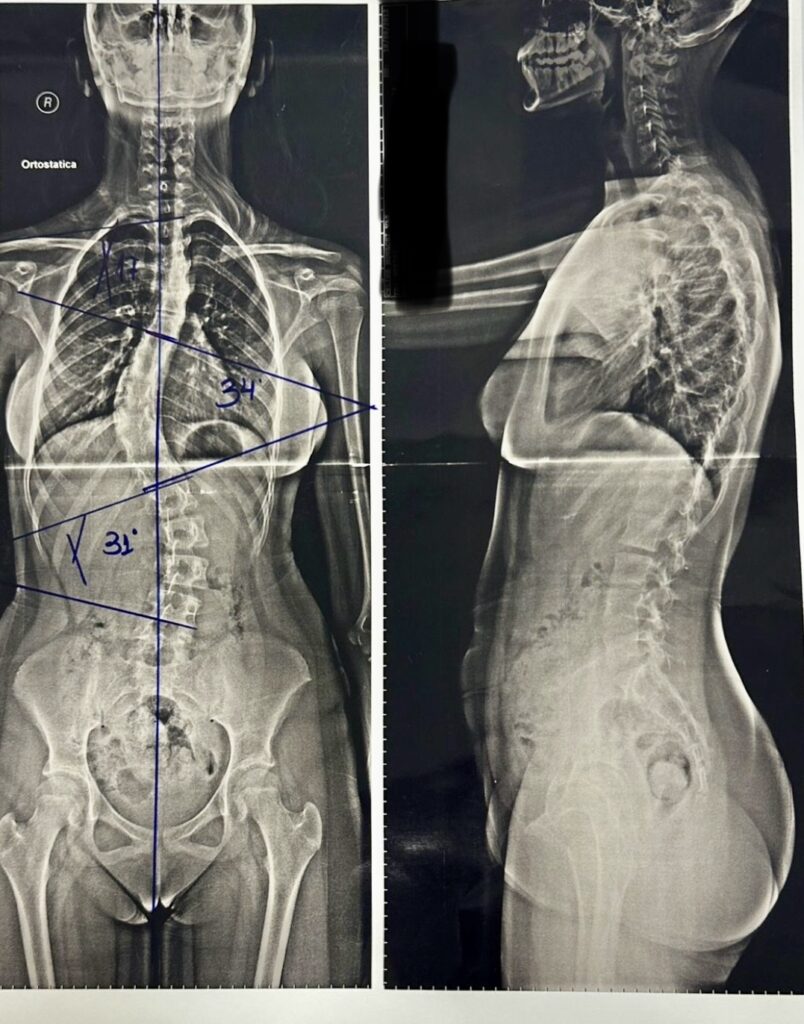

4. Radiografia panorâmica da coluna: confirma a presença e o grau da curva (medida pelo ângulo de Cobb);

Uma adolescente foi diagnosticada tardiamente com 16° de curva em um exame de raio-X de tórax. Sem acompanhamento e orientação adequada, sua curva evoluiu para mais de 60°, tornando-se caso cirúrgico.